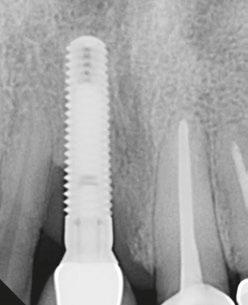

Figures 2A and 2B: 2A. Preoperative X-ray. 2B. Postoperative X-ray at 12 months. The LAPIP protocol is a tissue-sparing, non-destructive treatment that

Case courtesy of Larry Finkbeiner, DDS. Reproduced with permission

2A.

2B.